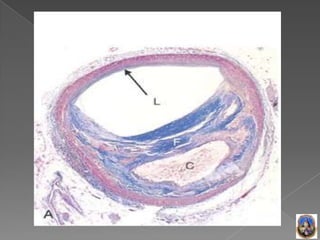

• 19.

 Estadio avanzado,invade la luz, y afecta al flujo  Componentes Fundamentales: I Células de Musculo liso, Macrófagos, Células Espumosas y Linfocitos T  II MEC con colágeno, fibras elásticas, proteoglicanos y cristales de calcio  III Lípidos intracelulares y extracelulares